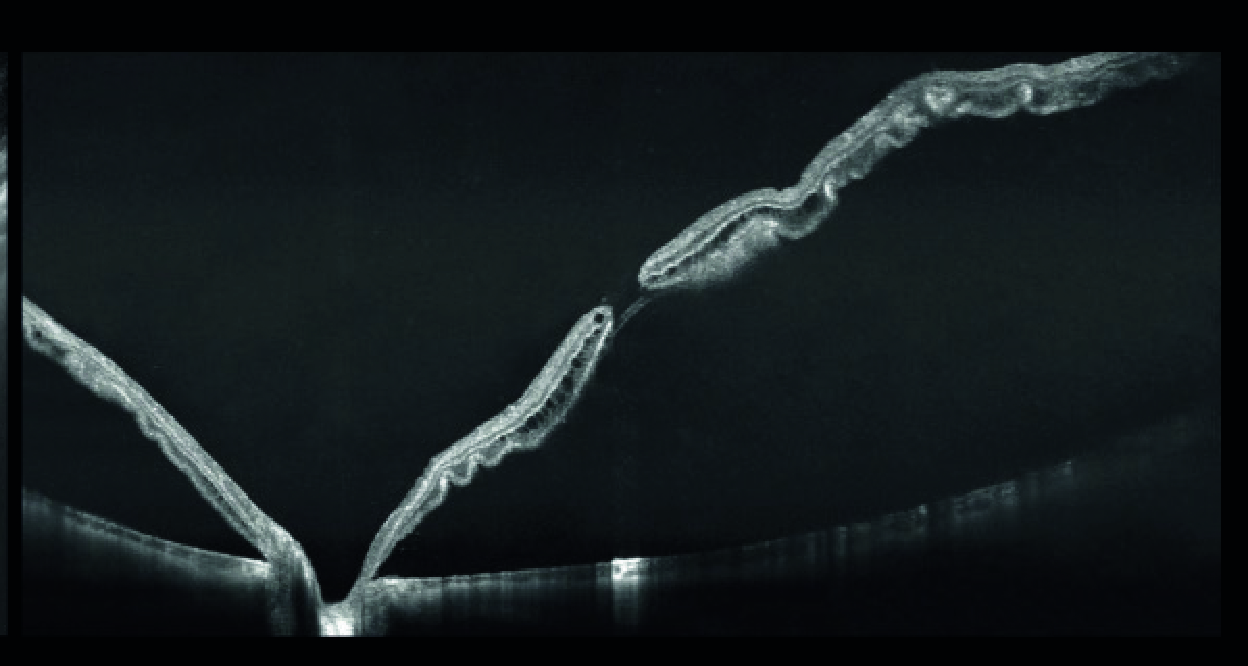

Визуализация с высокой детализацией сетчатки и хориоидеи | Центральная серозная хориоретинопатия